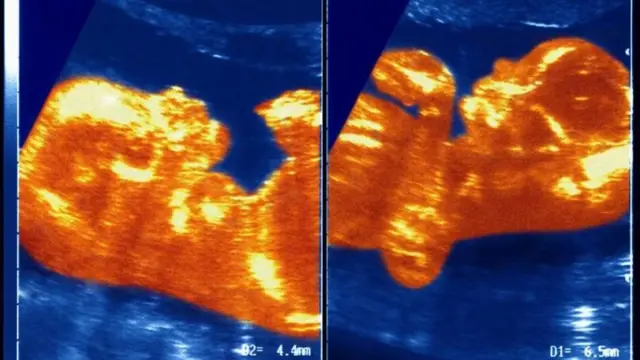

સંશોધકો માને છે કે અના પાઉલા ગર્ભમાં હતાં ત્યારે તેમના ભાઈના પ્લેસેન્ટા અને અનાના પ્લેસેન્ટા વચ્ચે કોઈ પ્રકારનો સંપર્ક થયો હતો, જેના કારણે રક્તવાહિનીઓ વચ્ચે જોડાણ થયું, જેના કારણે છોકરાનું લોહી છોકરી સુધી પહોંચી ગયું.

પ્રોફેસર માસિએલના મતે, "તેમાં એક ટ્રાન્સફ્યુઝન પ્રક્રિયા થઈ જેને આપણે ફીટલ-ફીટલ ટ્રાન્સફ્યુઝન કહીએ છીએ. કોઈક સમયે બંનેની નસો અને ધમનીઓ નાળમાં જોડાઈ ગઈ. ભાઈએ પોતાના રક્તથી જોડાયેલો પદાર્થ બહેનને આપી દીધો."